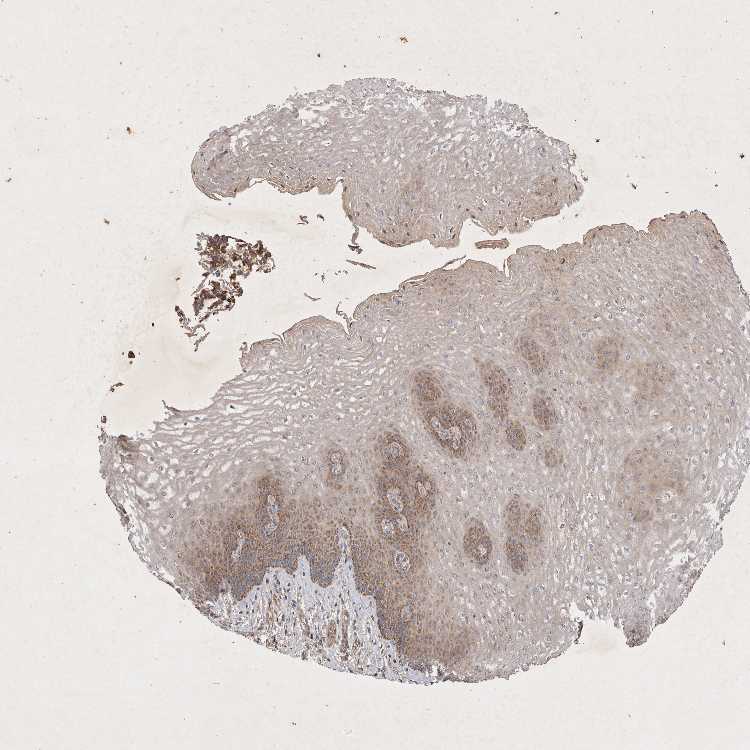

ESOPHAGUS - Antibody stainingi

Antibody staining in the annotated cell types in the current human tissue is reported as not detected, low, medium, or high, based on conventional immunohistochemistry profiling in selected tissues. This score is based on the combination of the staining intensity and fraction of stained cells.

Each image is clickable and will lead to virtual microscopy that enables deeper exploration of all samples and also displays staining intensity scores, fraction scores and subcellular localization as well as patient and tissue information for each sample.

Antibody HPA024550Antibody HPA027160

Squamous epithelial cells MediumMedium